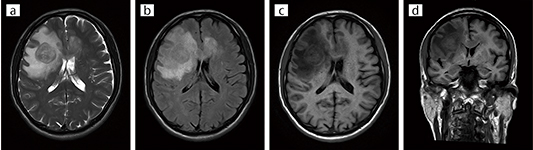

■臨床例1:脳腫瘍(Soft Sound ON)

Soft Sound で撮像した脳腫瘍症例。

さまざまなコントラストに使用できる。

a:T2 WI,AX,TR/TE = 3910 / 84,2 : 25

b:FLAIR,AX,TR/TE = 10000 / 96,2 : 41

c:T1 FLAIR,AX,TR/TE = 3497 / 14 . 8,2 : 06

d:T1 FLAIR,COR,TR/TE = 3497 / 14 . 8,3 : 02